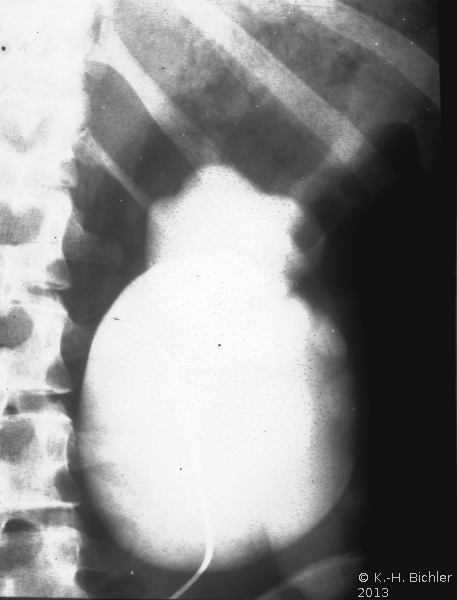

• Abbildung 17: Ureterabgangsstenose mit ausgedehnter Hydronephrose links

3. Retrograde Darstellung des hydronephrotischen linksseitigen Nierenbeckens